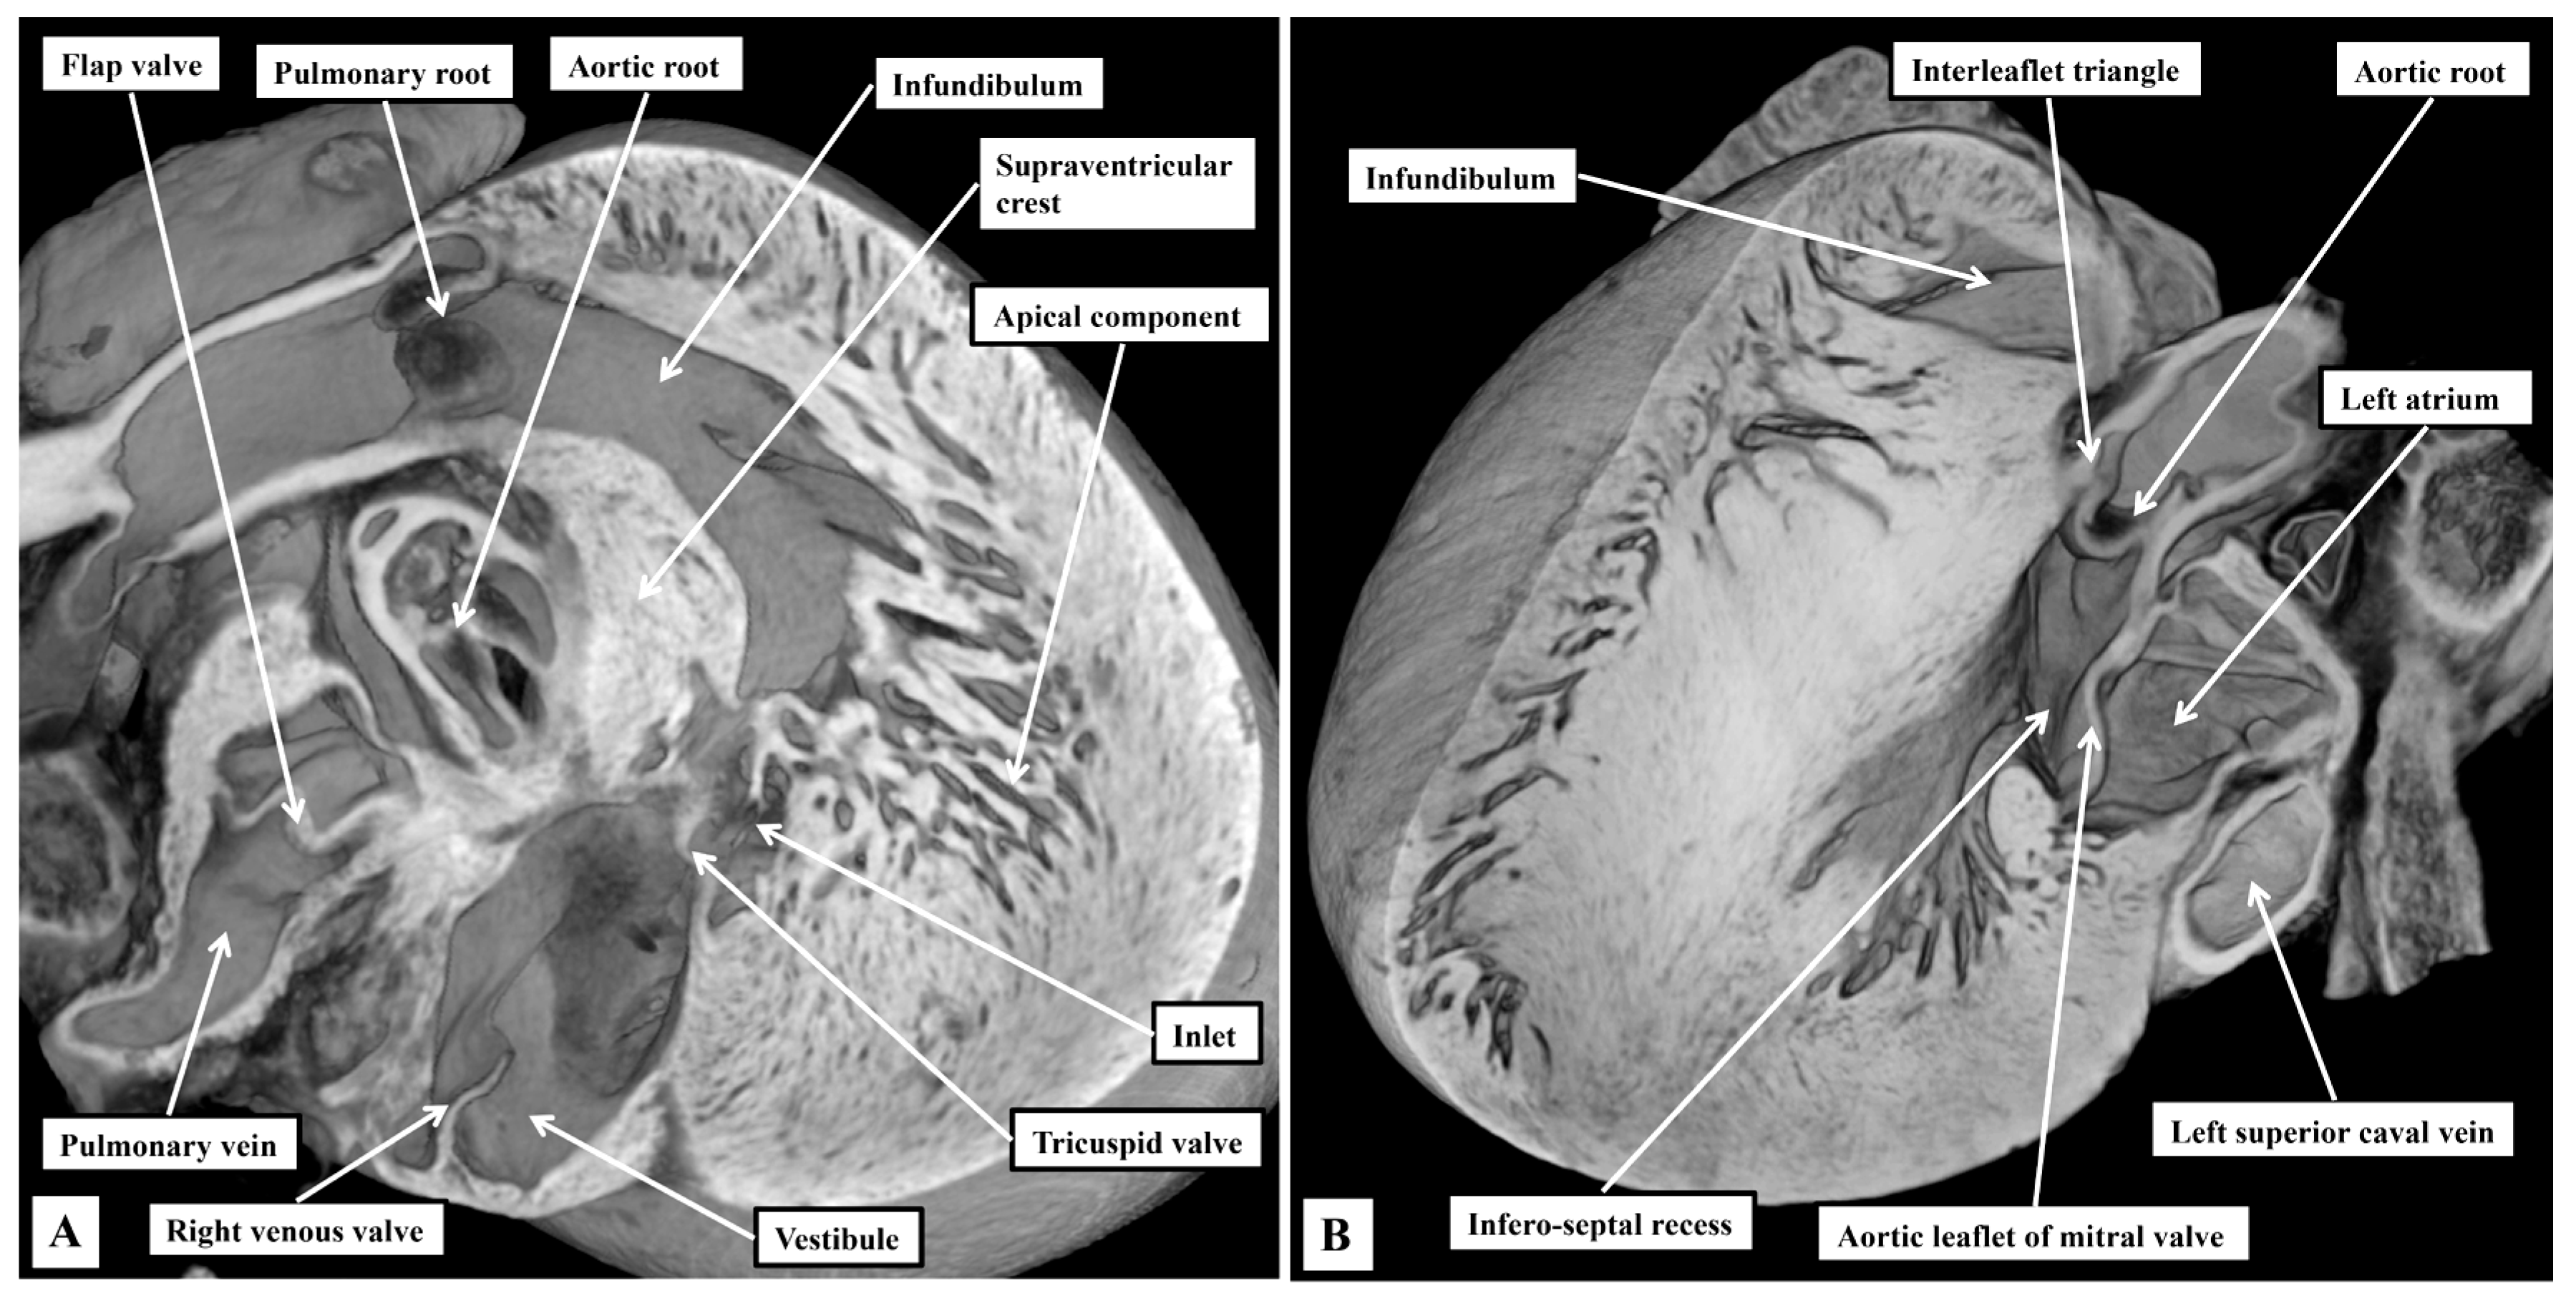

3.1. Gross Anatomy

3.2. The Arrangement of the Conduction Tissues